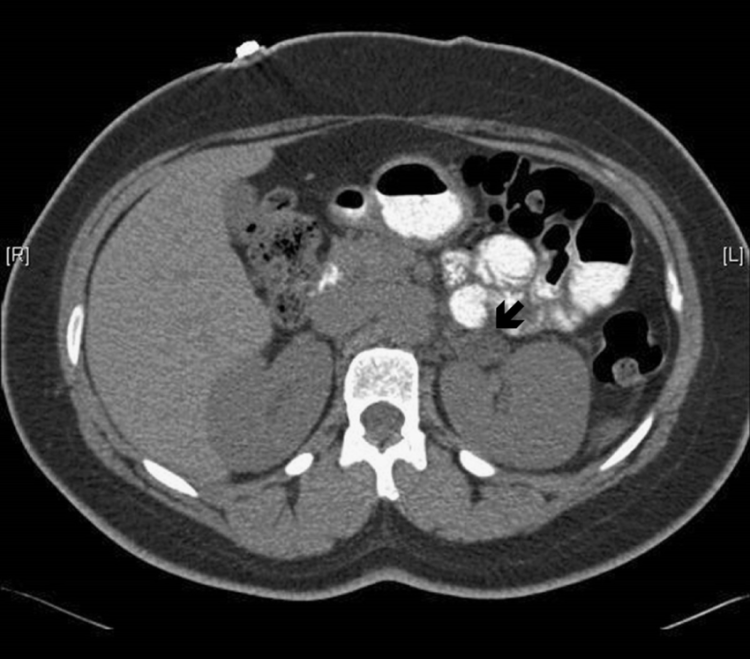

Hyperaldosteronism has been diagnosed historically by Adrenal Venous Sampling. It’s accomplished by running a catheter through the femoral vein up to each of the adrenal veins and sampling blood as it leaves the adrenal tissue. The amount and proportions of cortisol and aldosterone are compared. The method carries a risk of producing venal thrombosis and misdiagnosis is possible. If a diagnosis is made adenomas can be removed by laproscopic surgery. Bilateral hyperplasias can’t be removed surgically and need to be treated by medication and lifestyle. The CT images at the bottom of this post show the difference between the two, and demonstrate how difficult visual diagnosis can be.